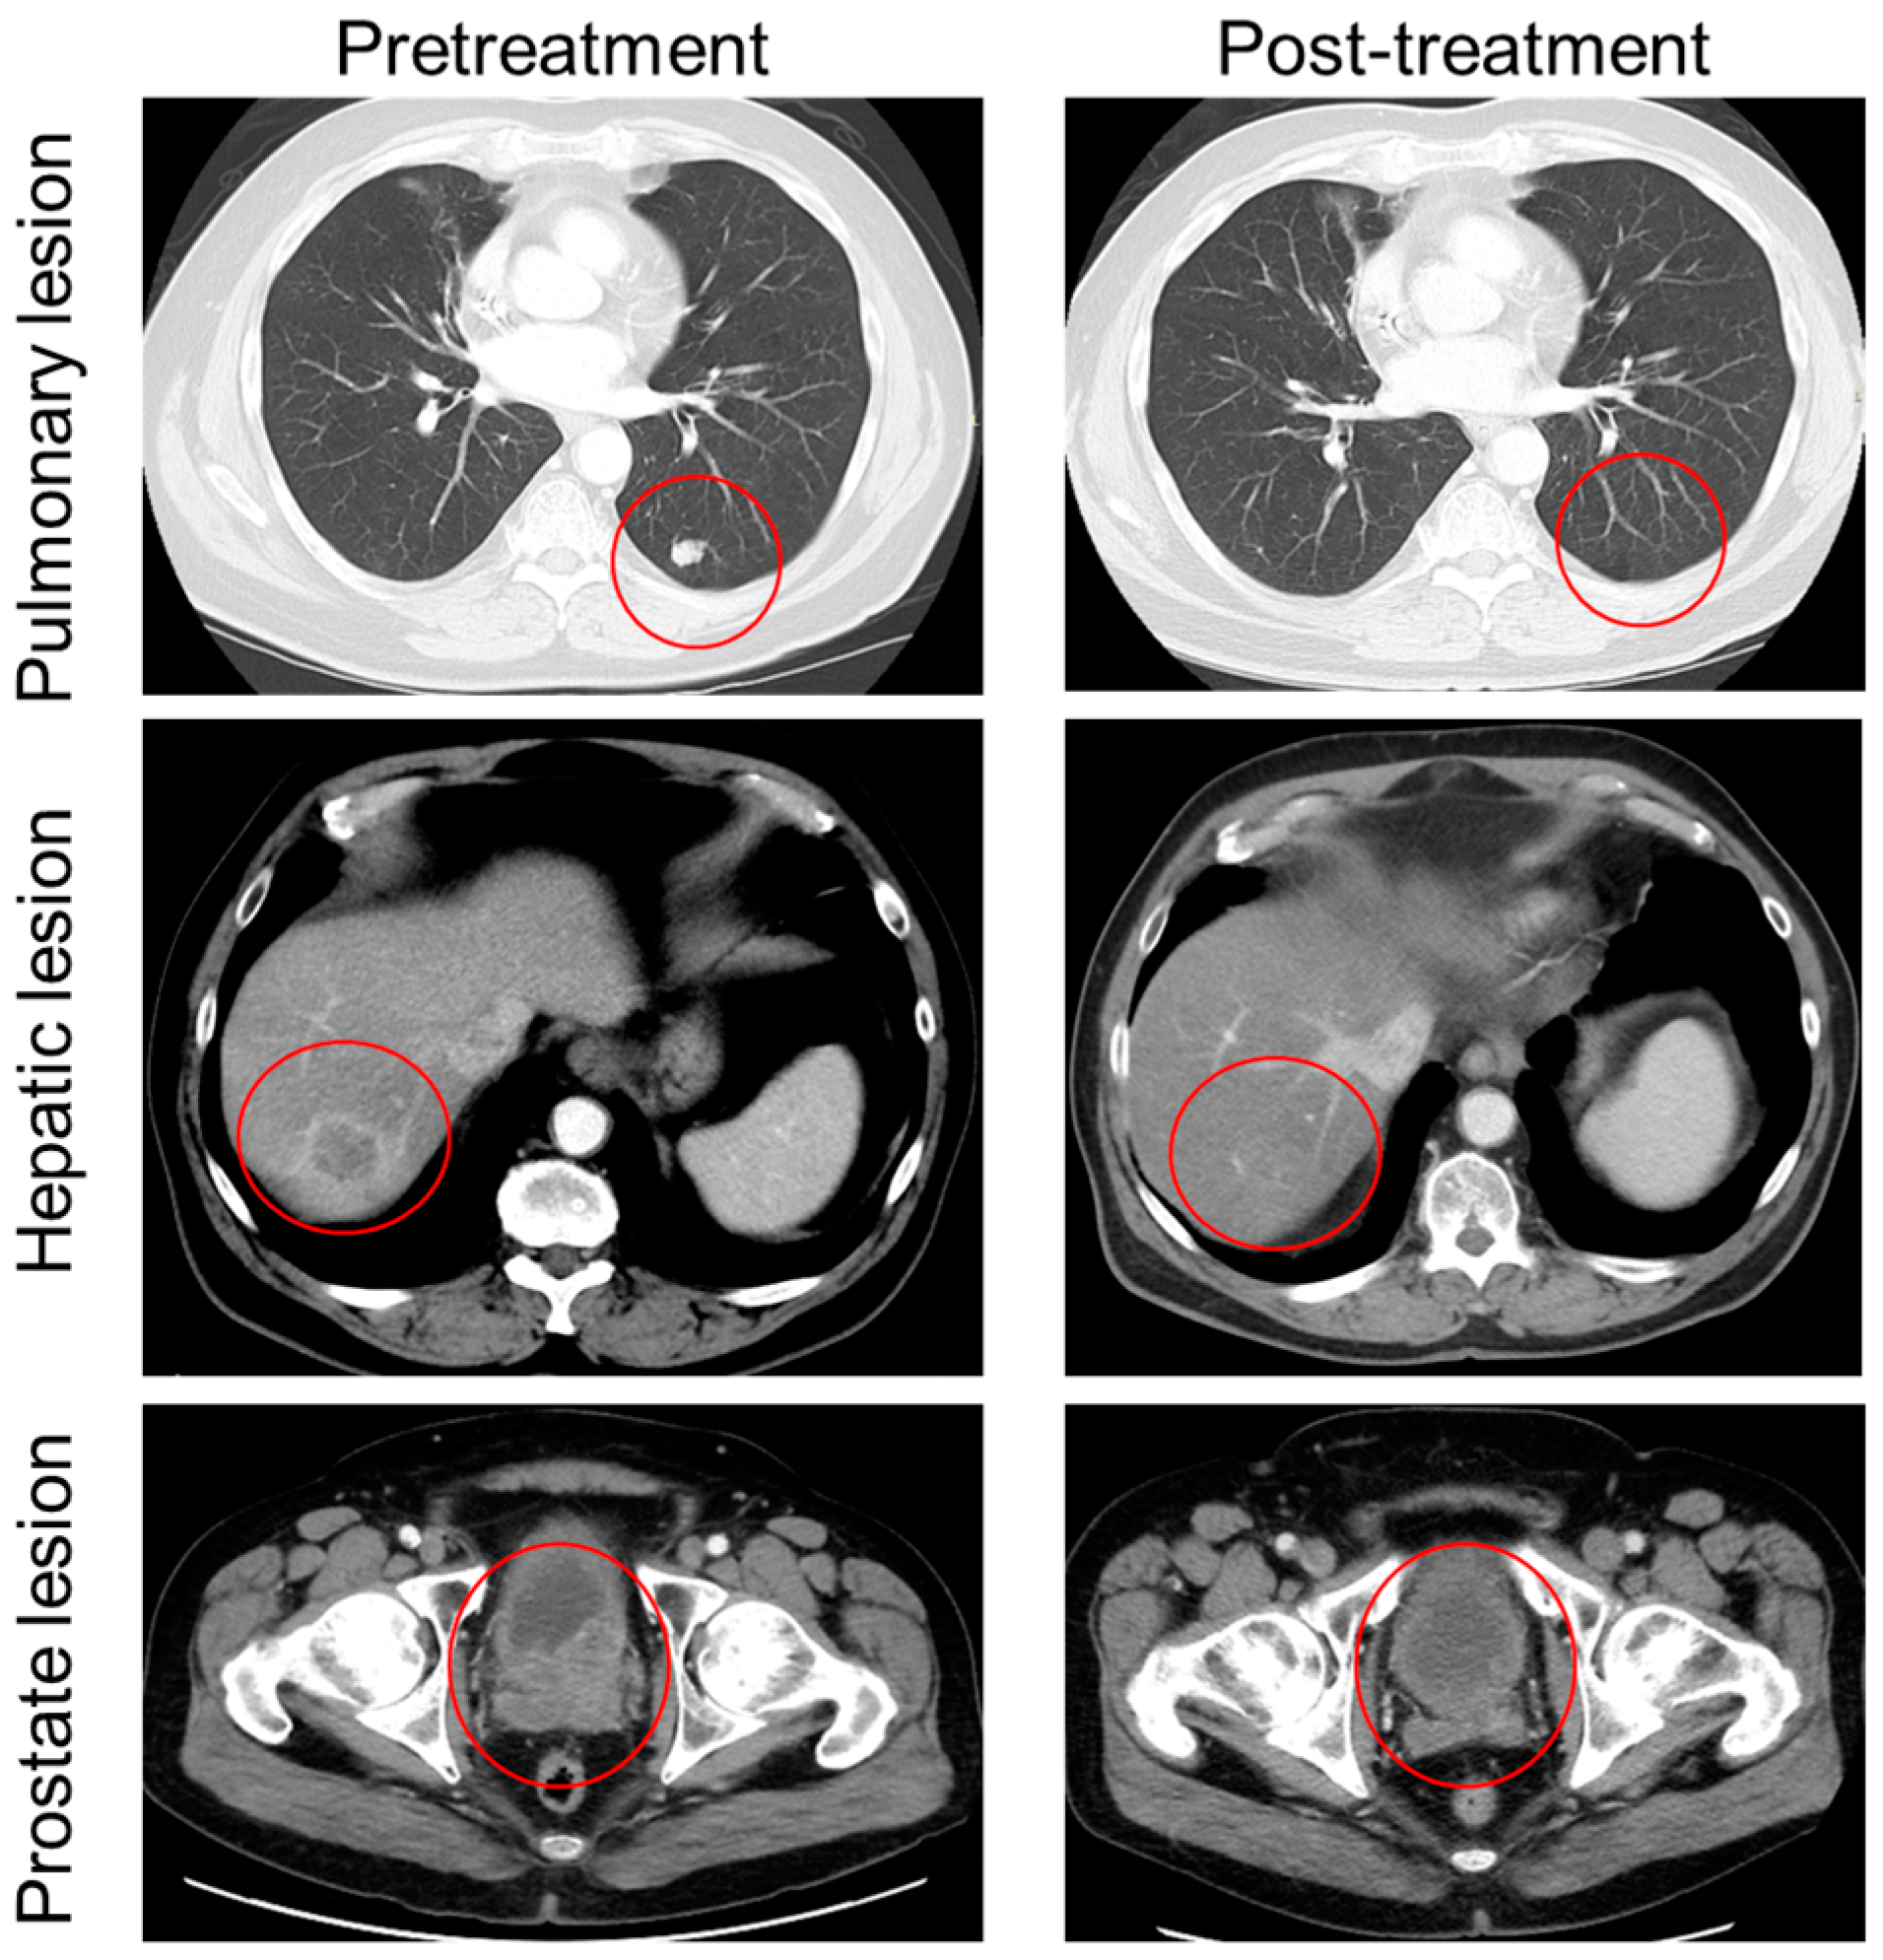

2. Case Description